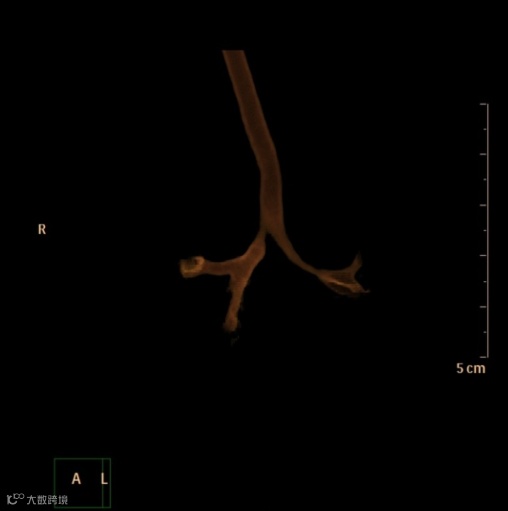

同一患者,CT体积渲染示气管下半部分明显偏向右侧,在左肺动脉异常通过处,气管腔突然变窄,图像如下。